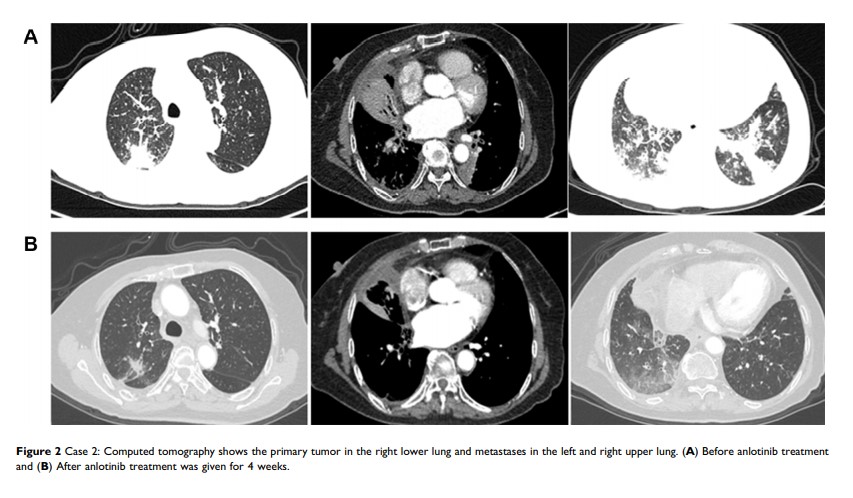

晚期非小细胞肺癌对安罗替尼的治疗反应与 TP53 突变之间的关联